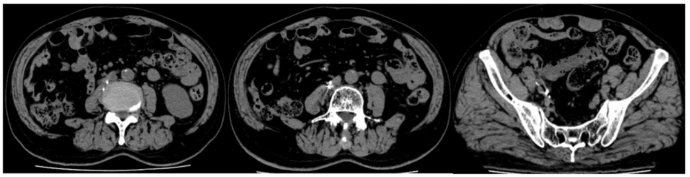

患者男,78岁。既往有高血压病史20余年,否认糖尿病、冠心病史,无吸烟史。2022年1月因"右腰部疼痛1月余"入院。1月15日行增强CT显示:右侧输尿管下端占位病变,考虑肿瘤。1月24日行腹腔镜下右肾、输尿管、部分膀胱切除术,术后病理显示:(右侧肾脏+输尿管+部分膀胱)输尿管高级别浸润性尿路上皮癌,脉管内查见癌栓,侵出外膜,未累及肾被膜及肾实质;膀胱断端未见肿瘤。术后规律行膀胱灌注联合免疫治疗:替雷利珠单抗注射液(PD-1单抗)。免疫治疗治疗期间病情进展,腹膜后及腹股沟淋巴结转移(图1A-C),行局部放射性粒子植入治疗(图1D-F),复查结果显示原腹膜后及右侧盆腔部分淋巴结已消失,残存淋巴结较前缩小,FDG代谢较前明显减低(图 1G-I)。

图1:免疫治疗治疗期间病情进展,腹膜后及腹股沟淋巴结转移(图1A-C),行局部放射性粒子植入治疗(图1D-F),复查结果显示原腹膜后及右侧盆腔部分淋巴结已消失,残存淋巴结较前缩小,FDG代谢较前明显减低(图 1G-I)